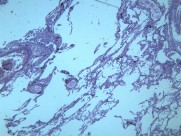

慢性支气管炎(chronic bronchitis)是由于感染或非感染因素引起气管、支气管粘膜及其周围组织的慢性非特异性炎症。其病理特点是支气管腺体增生、粘液分泌增多。临床出现有连续两年以上,每持续三个月以上的咳嗽、咳痰或气喘等症状。早期症状轻微,多在冬季发作,春暖后缓解;晚期炎症加重,症状长年存在,不分季节。疾病进展又可并发阻塞性肺气肿、肺源性心脏病,严重影响劳动力和健康。